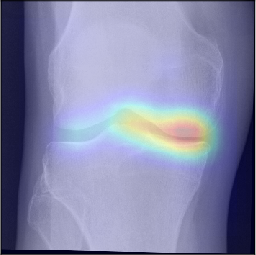

To gain insight into the basis of the CNN’s prediction, we used the GradCAM [24] approach and visualized the attention maps for the well-predicted knees. Examples of attention maps are presented in Figure 5. We observed that in various cases, the CNN paid attention to the compartment opposite to the one where degenerative change became visible during the follow-up visits. Additional examples of such attention maps are presented in Supplementary Figures 3, 4, 5 and 6.

Refer to caption

(a)

(b)

(c)

(d)

Figure 5: Examples of attention maps for progression cases and the corresponding visualization of progression derived using follow-up images from MOST datasets. Here, subplots (a) and (c) show the attention maps derived using a GradCAM approach. Subplots (b) and (d) show the joint-space areas from all the follow-up images (baseline to 84 months). Here, the subplot (b) corresponds to the attention map a) and the subplot (d) corresponds to the attention map (c).